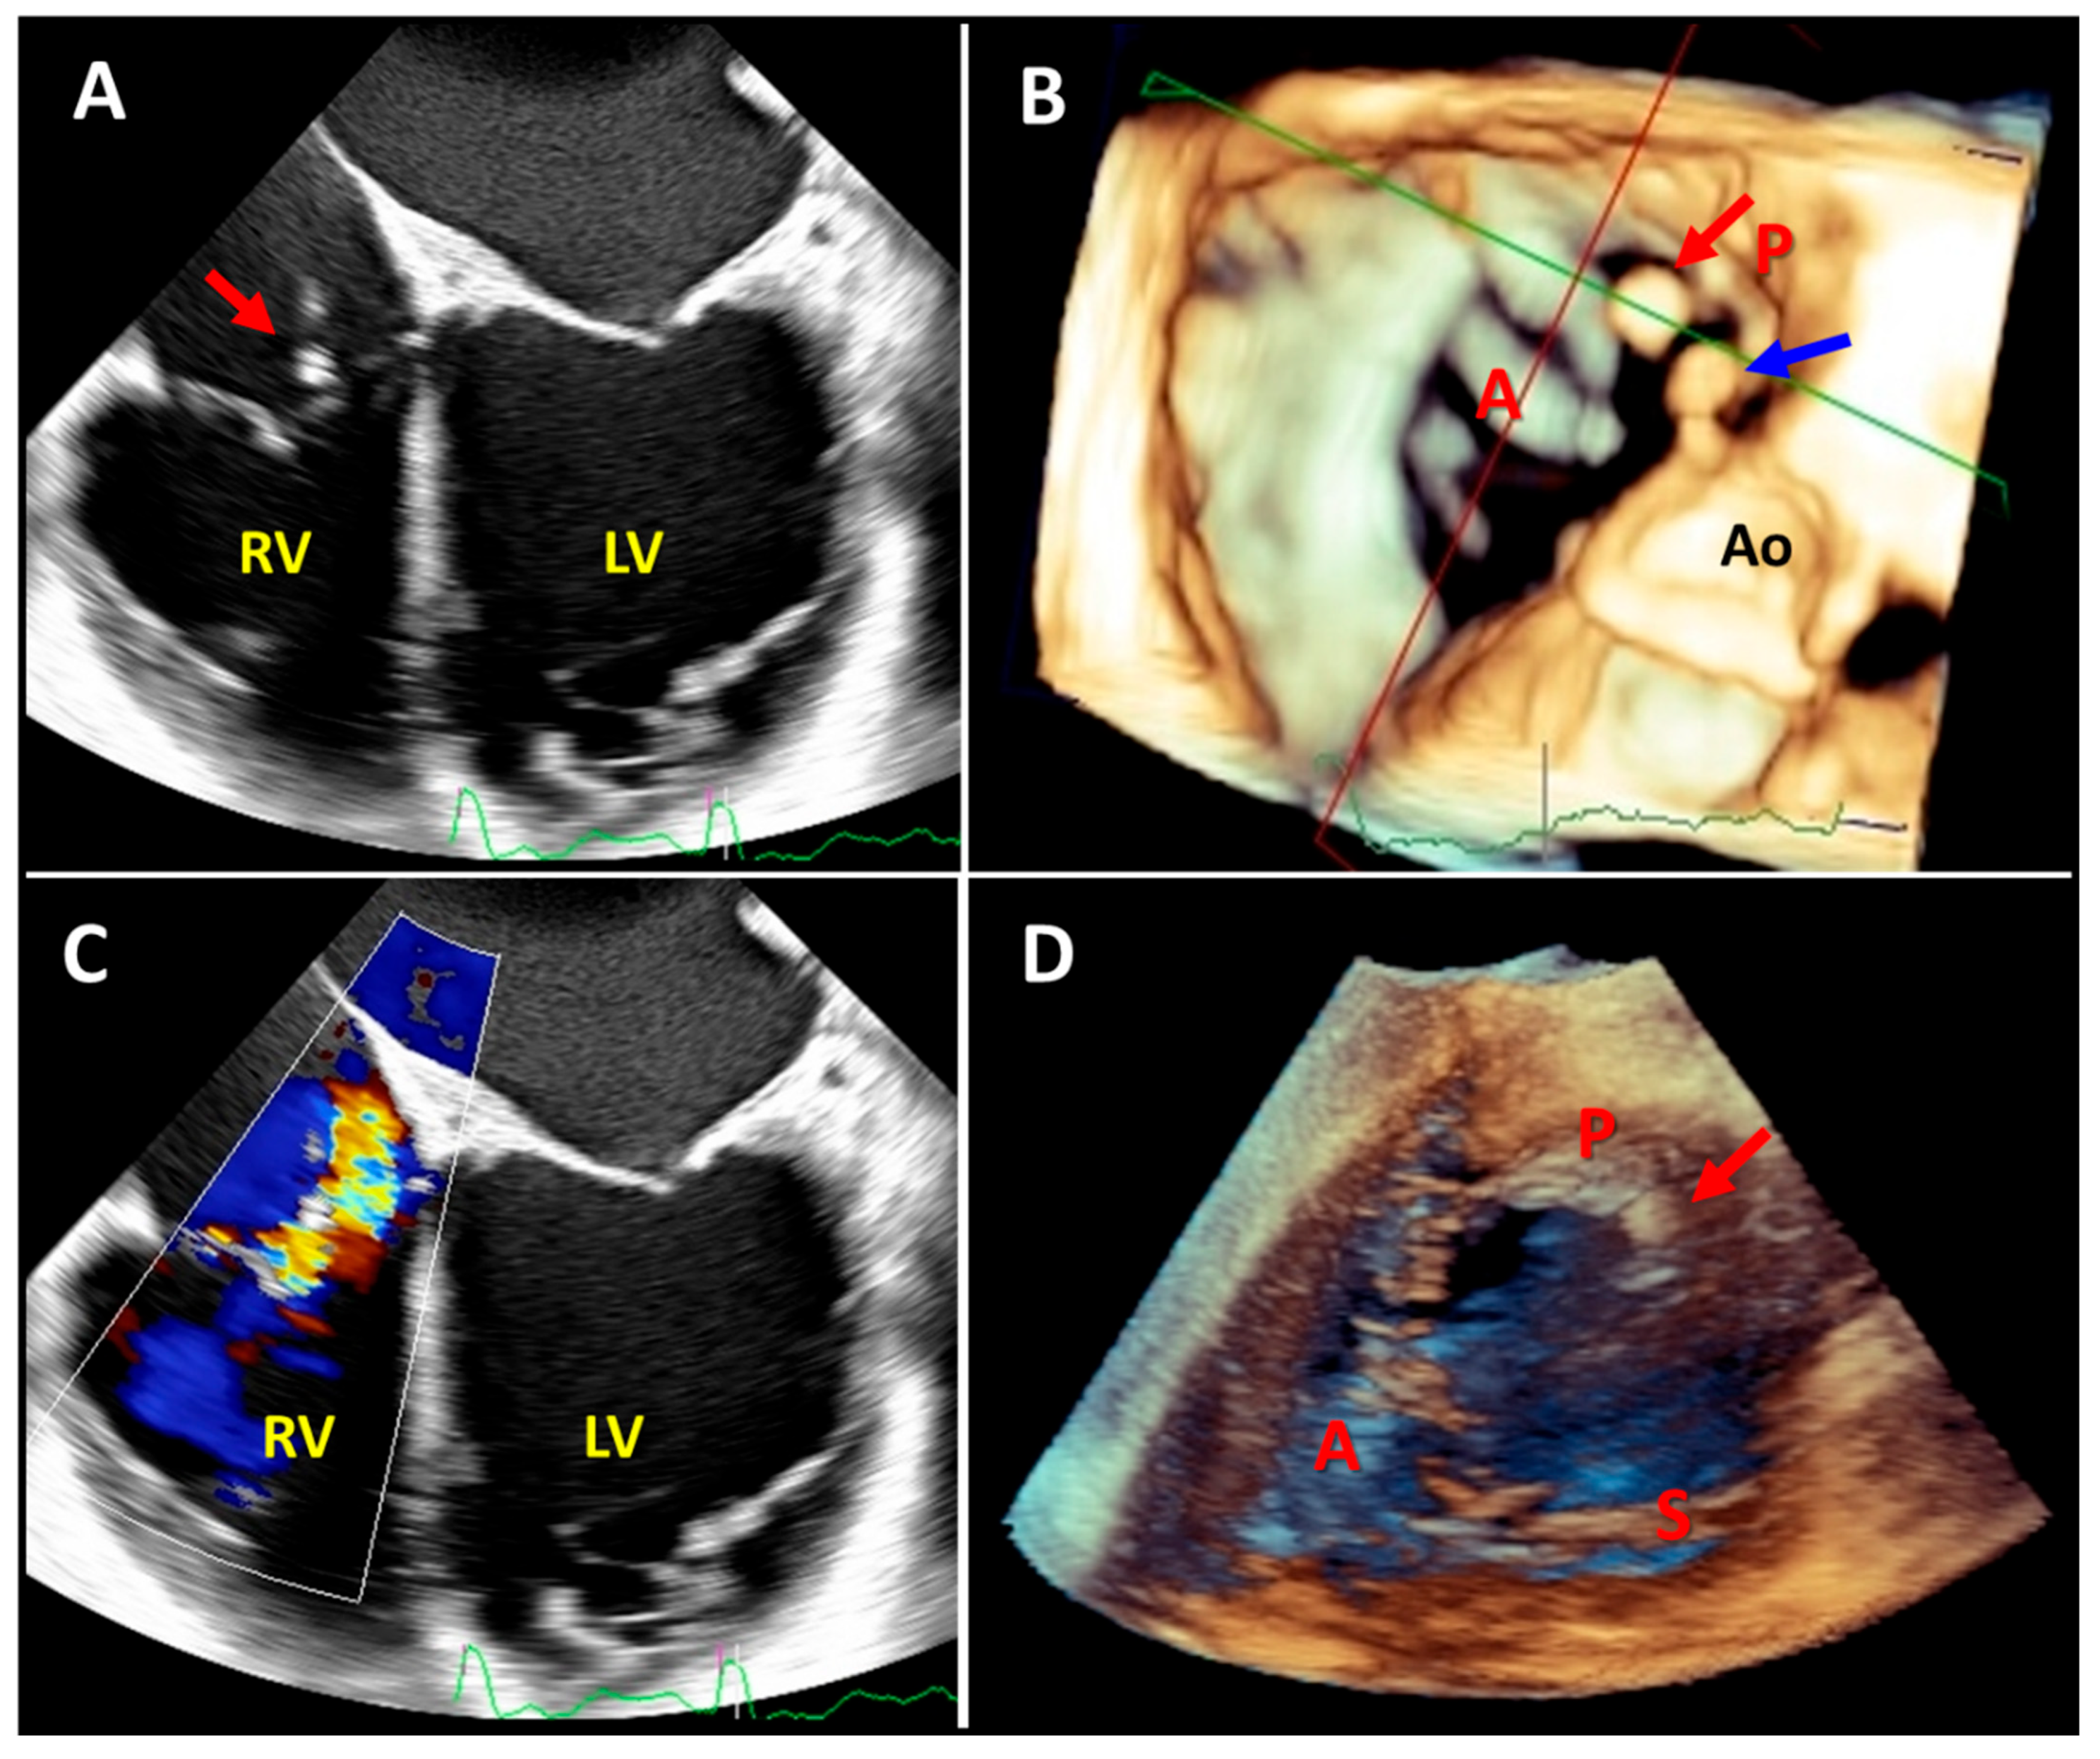

5. Three-Dimensional Echocardiography of the Right Ventricle and Tricuspid Valve

6. Added Value of 3D Echocardiography Compared to 2D Echocardiography in the Assessment of the Right Ventricle

6.2. RV Volume Overload